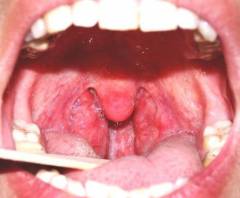

При остром тонзиллите больные обращаются к ЛОРу с жалобами на боли в горле и повышение температуры. Люди, страдающие хроническим тонзиллитом, жалуются на частые ангины, повторяющиеся от 1 до 6 раз в год. Для выявления их причины специалист проводит осмотр полости рта – фарингоскопию, во время которой он выявляет ряд характерных для фарингита симптомов.

- Покраснение передних и задних небных дужек. Их края гиперемированы и отечны.

- Отечность в области угла, образованного верхними краями передних и задних дужек.

- Покраснение и отечность миндалин.

- Увеличение миндалин. Они могут закрывать 1/3 или 1/2 просвета. Это может свидетельствовать об отеке при ангине, гипертрофическом хроническом тонзиллите или об особенностях анатомии. При отсутствии признаков воспаления размер миндалины значения не имеет. Также необходимо учитывать, что воспаленные миндалины, с заполненными гноем лакунами, могут быть атрофичны (уменьшены) и полностью скрываться за небными дужками.

- Гнойные выделения на миндалинах могут иметь вид:

- нагноившихся фолликулов;

- гнойных пробок в просвете лакун или жидкого гноя, выделяющегося из них при надавливании шпателем;

- гнойного налета на поверхности миндалин, который не распространяется за ее пределы.